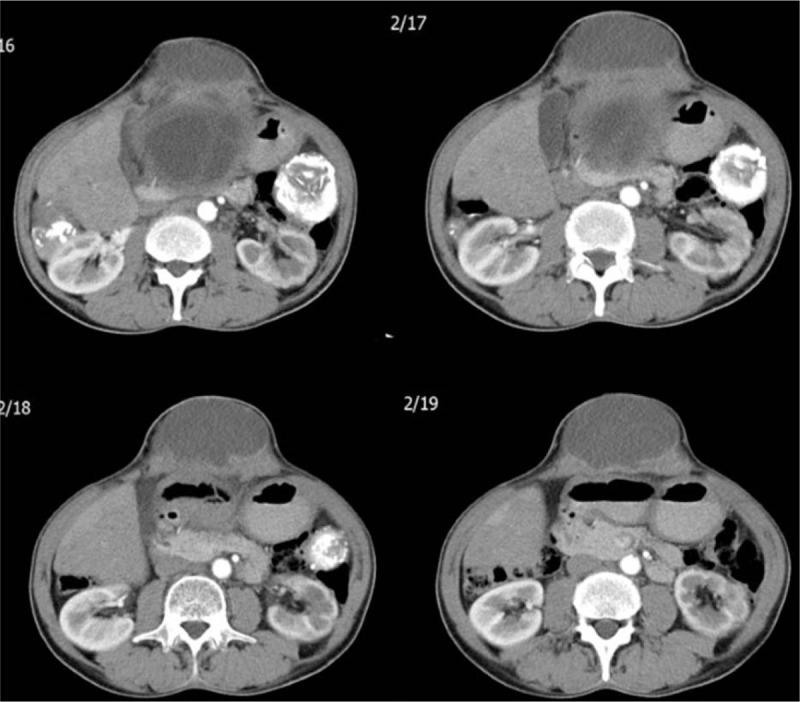

According to PRISMA guidelines a literature search was made in PubMed, Medline, Google Scholar, and Google databases were searched using keywords to identify articles related to cutaneous fistulization of the HD. Keywords used were hydatid disease, hydatid cyst, cutaneous fistulization, cysto-cutaneous fistulization, external rupture, and external fistulization. The literature search included case reports, review articles, original articles, and meeting presentations published until July 2016 without restrictions on language, journal, or country. Articles and abstracts containing adequate information, such as age, sex, cyst size, cyst location, clinical presentation, fistula opening location, and management, were included in the study, whereas articles with insufficient clinical and demographic data were excluded. We also present a new case of cysto-cutaneous fistulization of a liver hydatid cyst.

The literature review included 38 articles (32 full text, 2 abstracts, and 4 unavailable) on cutaneous fistulization in patients with HD. Among the 38 articles included in the study, 22 were written in English, 13 in French, 1 in German, 1 in Italian, and 1 in Spanish. Forty patients (21 males and 19 females; mean age ± standard deviation, 54.0 ± 21.5 years; range, 7-93 years) were involved in the study. Twenty-four patients had cysto-cutaneous fistulization (Echinococcus granulosus); 10 had cutaneous fistulization (E multilocularis), 3 had cysto-cutaneo-bronchio-biliary fistulization, 2 had cysto-cutaneo-bronchial fistulization; and 1 had cutaneo-bronchial fistulization (E multilocularis). Twenty-nine patients were diagnosed with E granulosis and 11 had E multilocularis detected by clinical, radiological, and/or histopathological examinations.